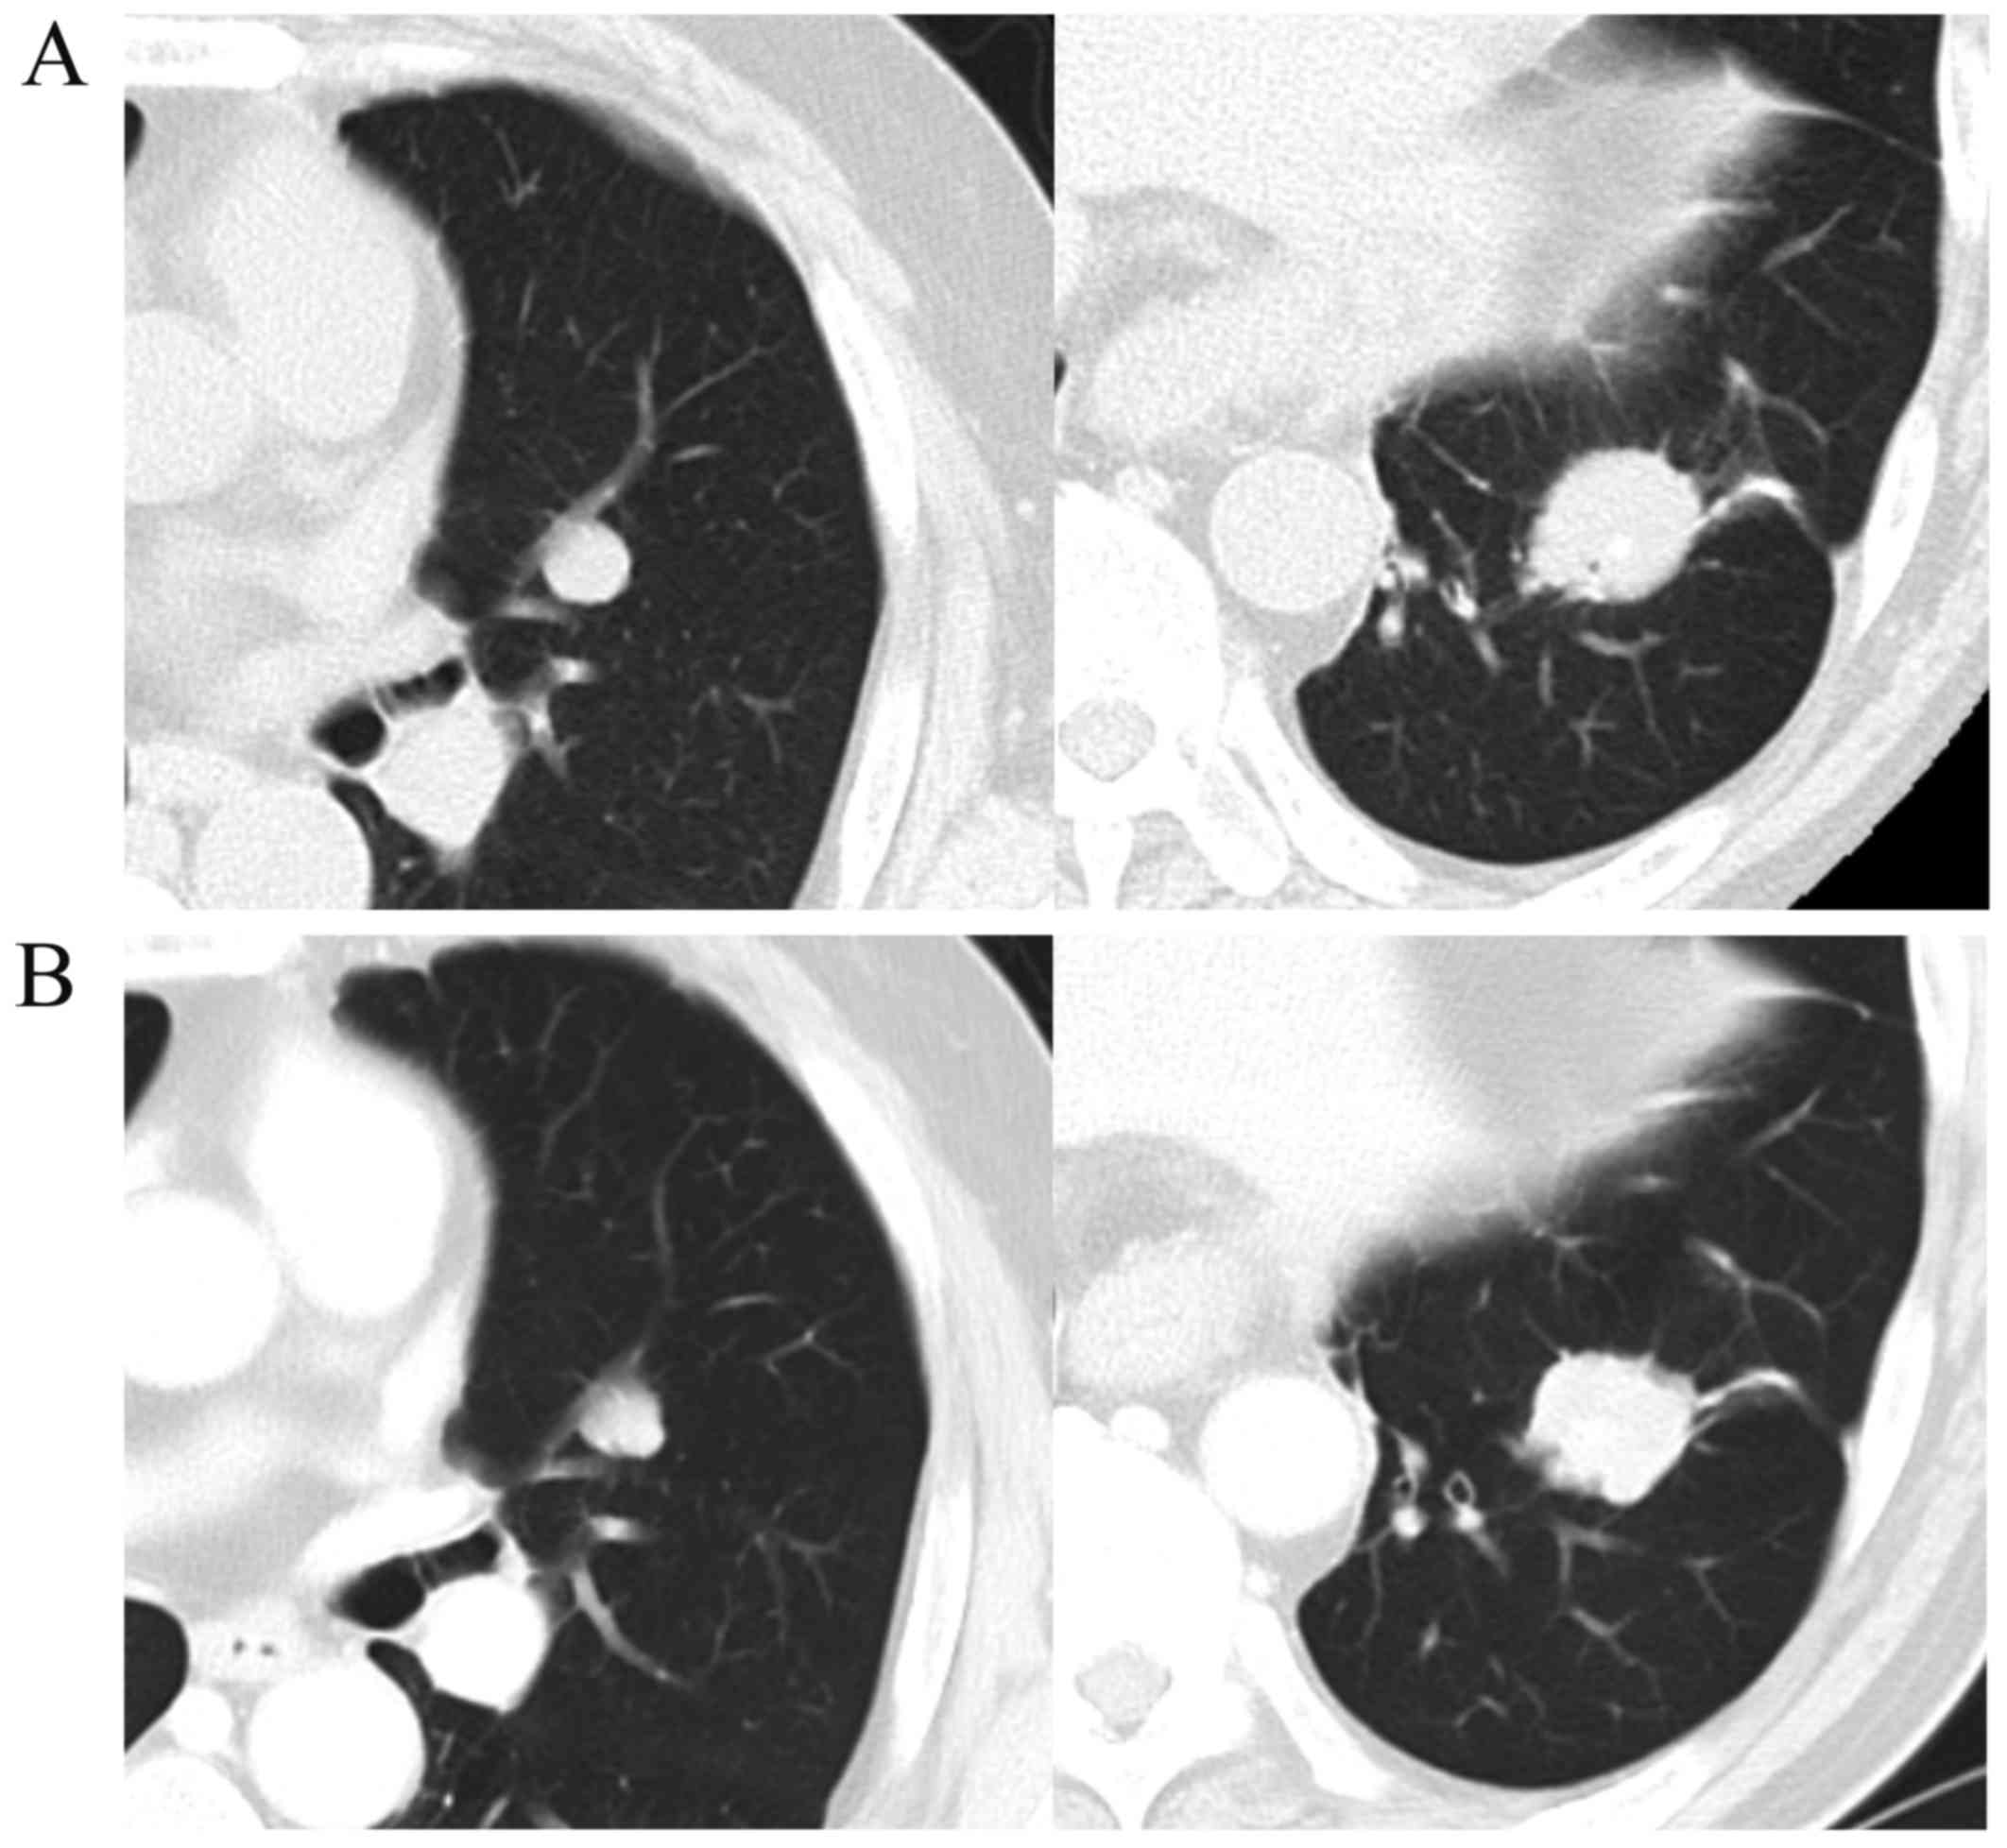

Salivary duct carcinoma is a highly aggressive disease with a poor prognosis. Surgical resection is currently the only curative treatment, as there is no effective systemic therapy for this malignancy. Recently, trastuzumab has been shown to exhibit therapeutic efficacy in the treatment of salivary duct carcinoma; similarly, molecularly targeted agents, such as cetuximab, are expected to be useful for salivary duct carcinoma treatment. We herein describe the case of a 56-year-old man diagnosed with salivary duct carcinoma in the left submandibular region, with ipsilateral multiple metastases to the neck lymph nodes. Radical resection of the tumor and submandibular gland with neck dissection were performed. One month after radical surgery, computed tomography (CT) scans indicated metastasis in the lower lobe of the left lung. CT‑guided transthoracic fine‑needle aspiration biopsy revealed a single metastasis and lung metastasectomy was immediately performed. The tumor cells of the primary lesion and those of the lung metastasis were immunohistochemically positive for epidermal growth factor receptor. One month later, multiple right lung metastases appeared, and the patient was treated with cisplatin/5‑fluorouracil (5‑FU) chemotherapy plus cetuximab, achieving a complete radiographic response. However, multiple lung metastases developed during adjuvant weekly cetuximab monotherapy. Subsequently, treatment with S‑1 and weekly cetuximab was initiated, and the multiple lung metastases have been maintained as stable disease for 5 months. To the best of our knowledge, this is the first report of cetuximab use for the treatment of salivary duct carcinoma. Although cisplatin/5‑FU chemotherapy plus cetuximab was efficacious in treating the lung metastasis, cetuximab monotherapy was insufficient for controlling tumor growth.